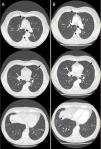

Our patient was a 67-year-old man who had quit smoking 25 years previously (cumulative dose: 20 pack-years), with no other significant history. He was admitted for mild COVID-19 pneumonia (oxygen therapy 2–3l/min) and treated with remdesivir and dexamethasone 8mg/day for 10 days, and discharged with a protocolized tapering prednisone regimen. A high-resolution chest CT scan at 2 months (Fig. 1A) showed multiple solid bilateral pulmonary nodules measuring less than 1cm and some atelectasis and fibrosis.

Multiple nodules observed on high-resolution computed tomography in patients with COVID-19 has been described previously.1 However, the delayed appearance of multiple solid nodules of mild COVID-19 pneumonias without other inflammatory findings is atypical, and requires a differential diagnosis with neoproliferative and infectious processes. However, due to the patient's satisfactory clinical recovery and lack of reason for concern, we decided to prescribe prednisone 5mg/day and repeat a high-resolution chest CT scan at 3 months (Fig. 1B), which showed progressive resolution of nodules. Although no pathology study was available, given the radiological progress and the clinical context, the diagnosis was organizing foci, which is an uncommon radiological presentation of organizing pneumonia.2